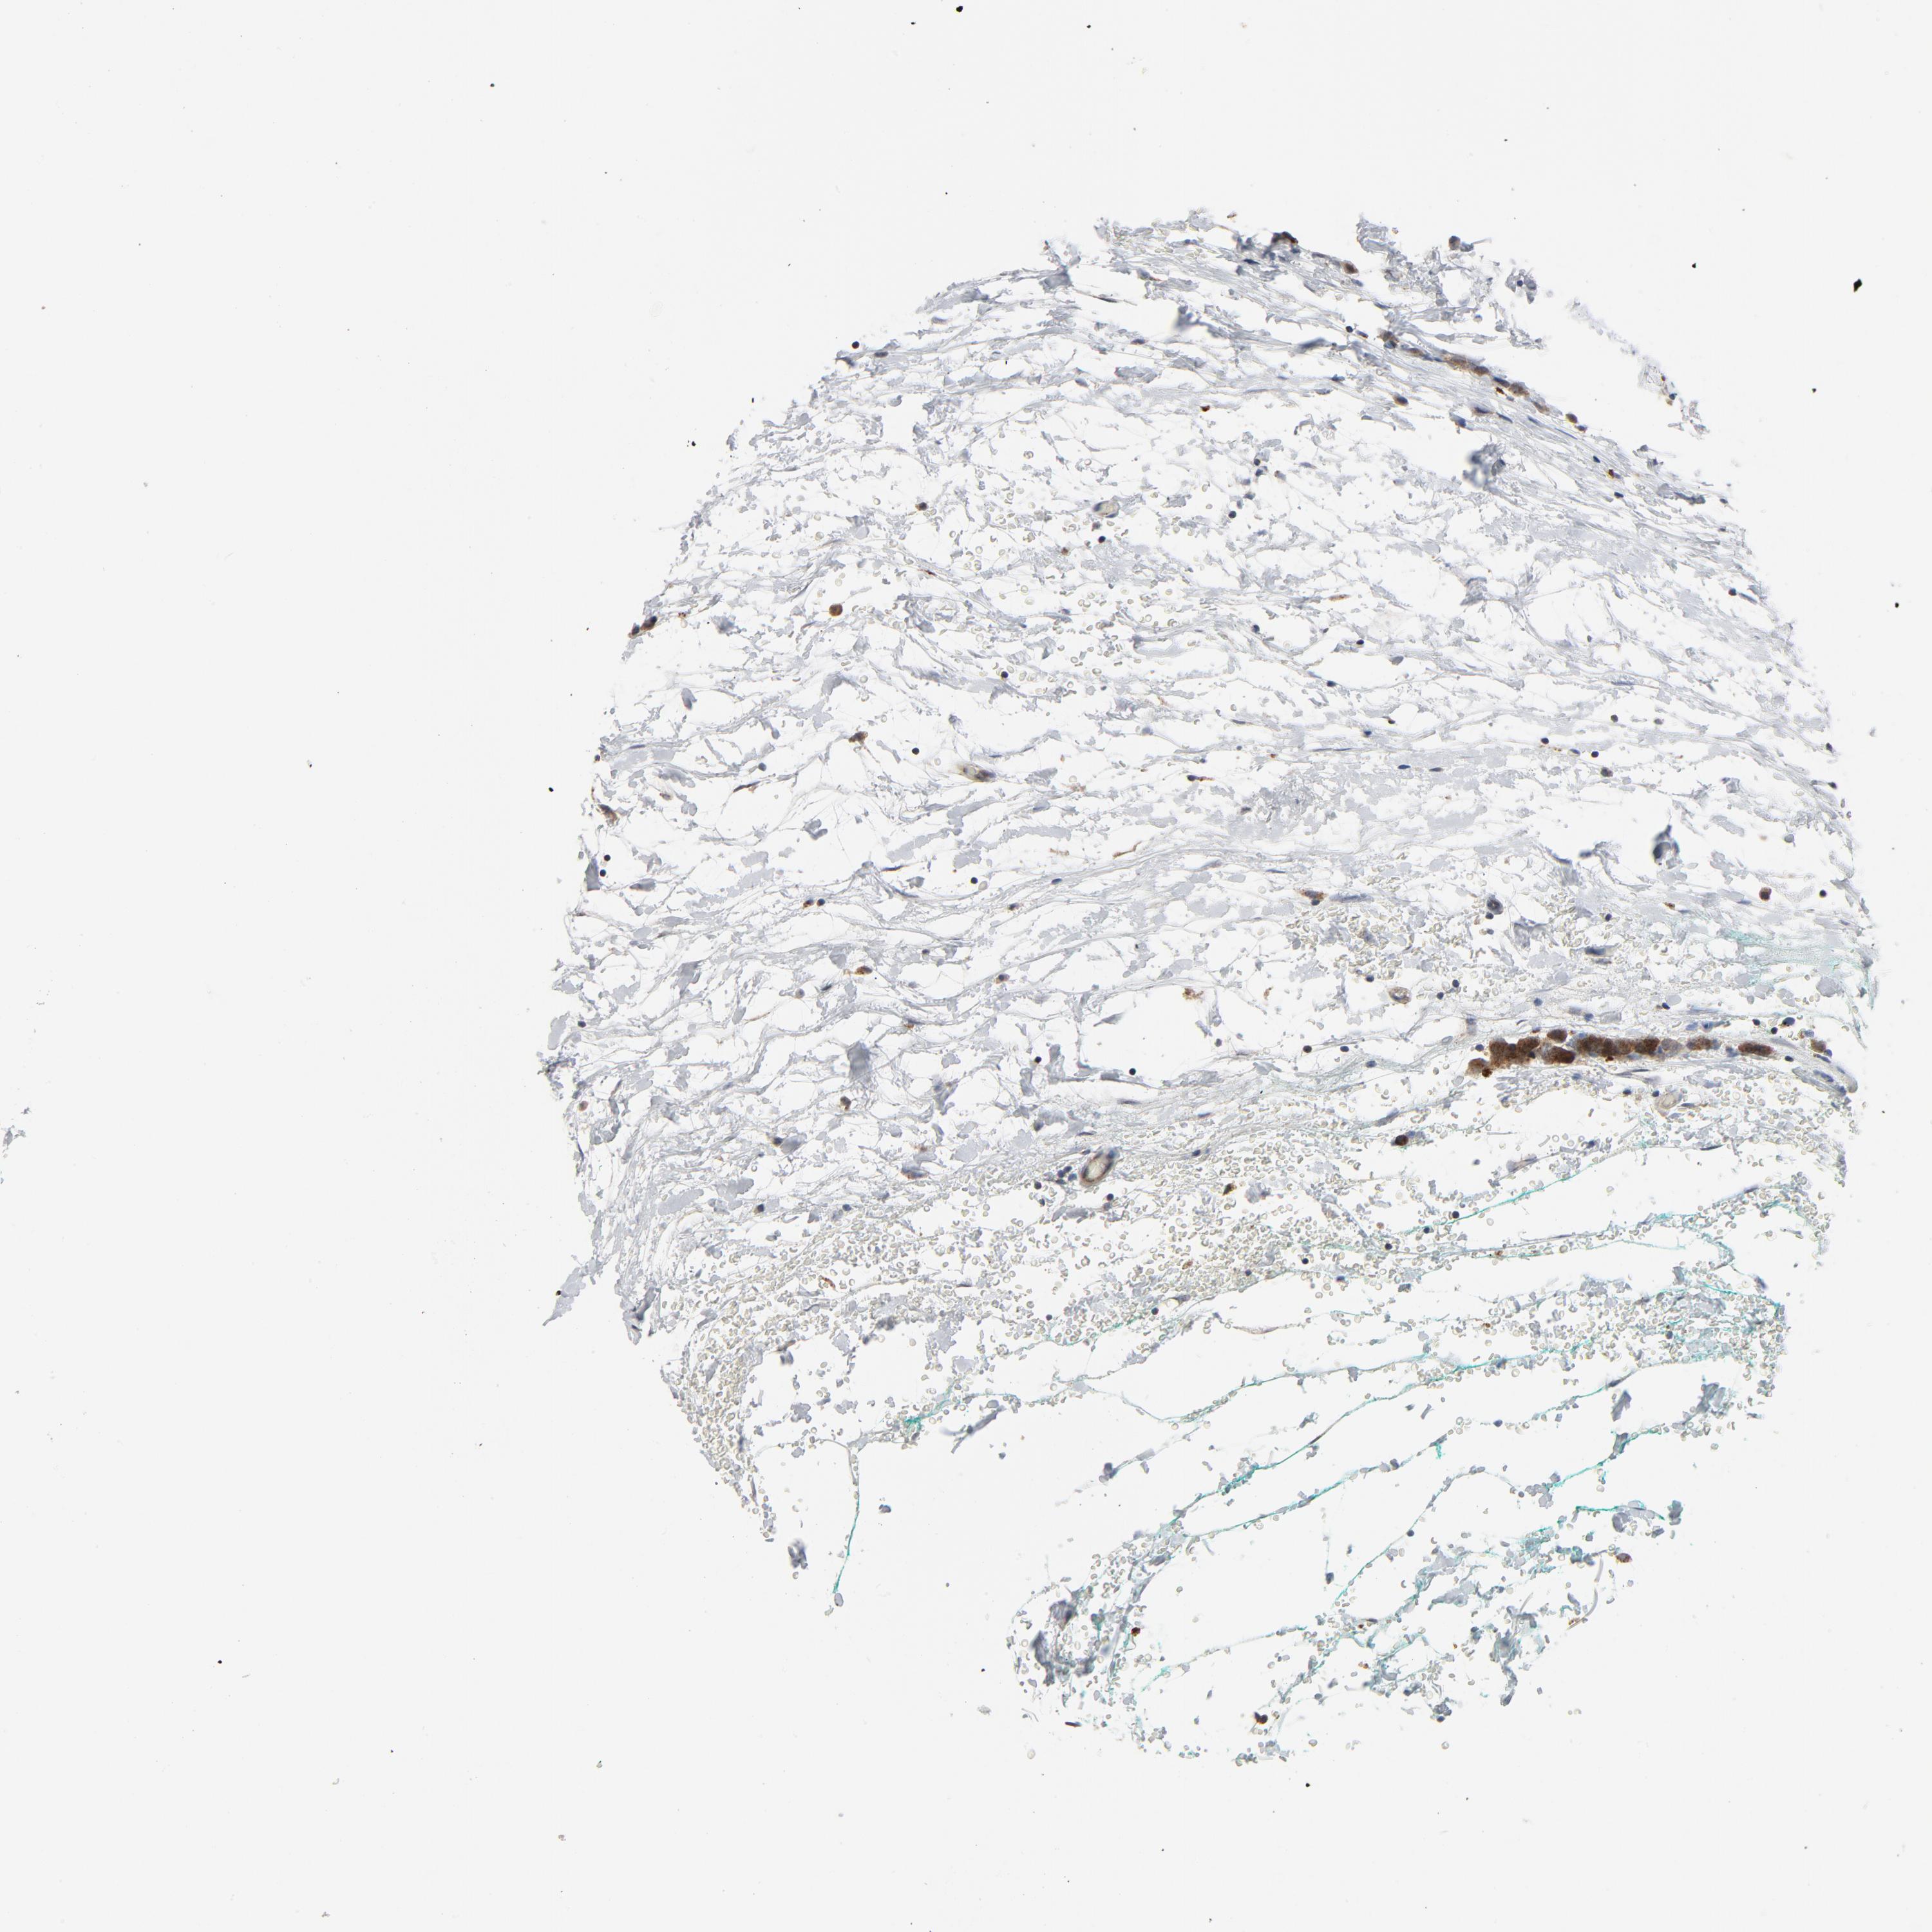

BRCA TCGA BRCA VALIDATION PROTEIN EXPRESSION